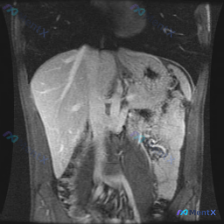

各位同道好!最近碰到一份影像读片申请,临床直指「脾脏病变」,但拿到的仅为一张腹部MRI冠状位T2序列图。先整理一下影像科的初步描述和我的分析思路,抛砖引玉和大家讨论。 --- 一、先看影像科给出的「表面事实」 1. 肝脏:形态、实质信号大致均匀,门脉、肝静脉走行清,无明显局灶性高低信号。 2. 脾脏...